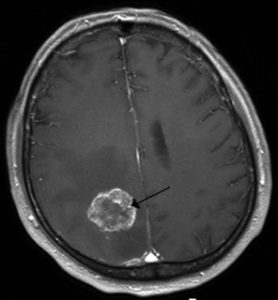

Here is an interesting scientific study. It is not regarding radiation directly from a smart meter, but it is a test of similar frequencies of microwave radiation from a cell phone causing brain tumors. The study shows a potential increase in brain tumors in the frontal lobe of the brain, which is where a cell phone sits up against. Here is the study: RF Radiation Brain Tumor Risk Study